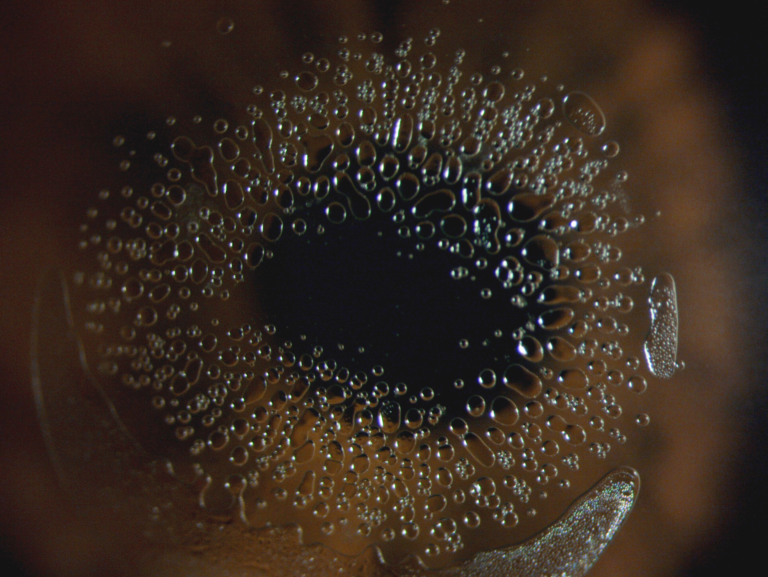

Second place - Keyur Patel, Doctor of Optometry, Tompkins Knight and Son Optometrists, Northampton

Keyur Patel claimed second prize with his striking image capturing bubbles under the orthokeratology lens.

Judge Nicola Bennett, Head of Clinical Education at Keeler said of the 2nd place entry, “Keyur Patel’s image has exceptional clarity, demonstrating remarkable technique and attention to detail”.